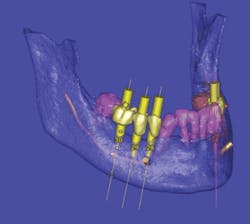

Specialized 3–D reconstructive software also allows practitioners to provide 3–D images and viewer software to the referring dentist, allowing for collaboration regarding positioning, placement, and angulation of implants prior to surgical placement procedures (Fig. 3).